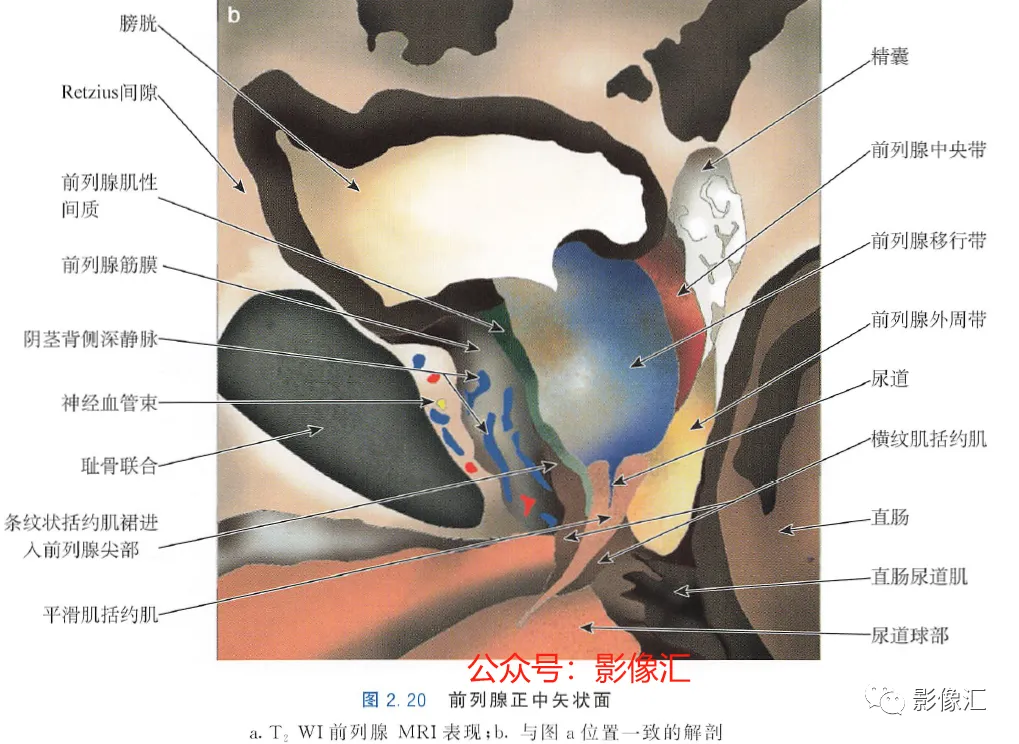

2. 正中矢状面(图2.20)